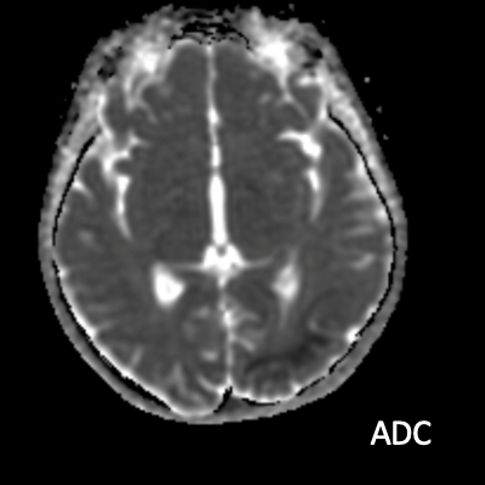

- A) Aksiyel FLAIR görüntülerde parietooksipital lobda kortikal hiperintensite (ok) ve difüzyon görüntülerde kısıtlanma alanları izleniyor (oklar). Ertesi gün çekilen kontrol MRG’de FLAIR serilerde yeni gelişen oksipital bölgede kortikal hiperintensite (ok) izlenmektedir.

- MRG’de akut fazda T2/FLAIR hiperintensiteyle birlikte giral şişme ile karakterize enfarkt-benzeri lezyonlar ve subkortikal beyaz cevher tutulumu görülür. DWI’da artmış sinyal dikkat çekmekle birlikte ADC değerlerinin normal ya da hafif artmış olması, baskın sürecin vazojenik ödem olduğunu gösterir.